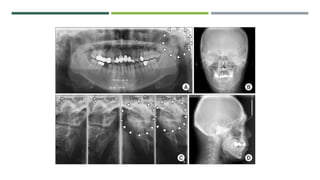

LATERAL TOMOGRAPHIC SECTION

CT – SCANS OF TMJ

Coronal section

Axial section